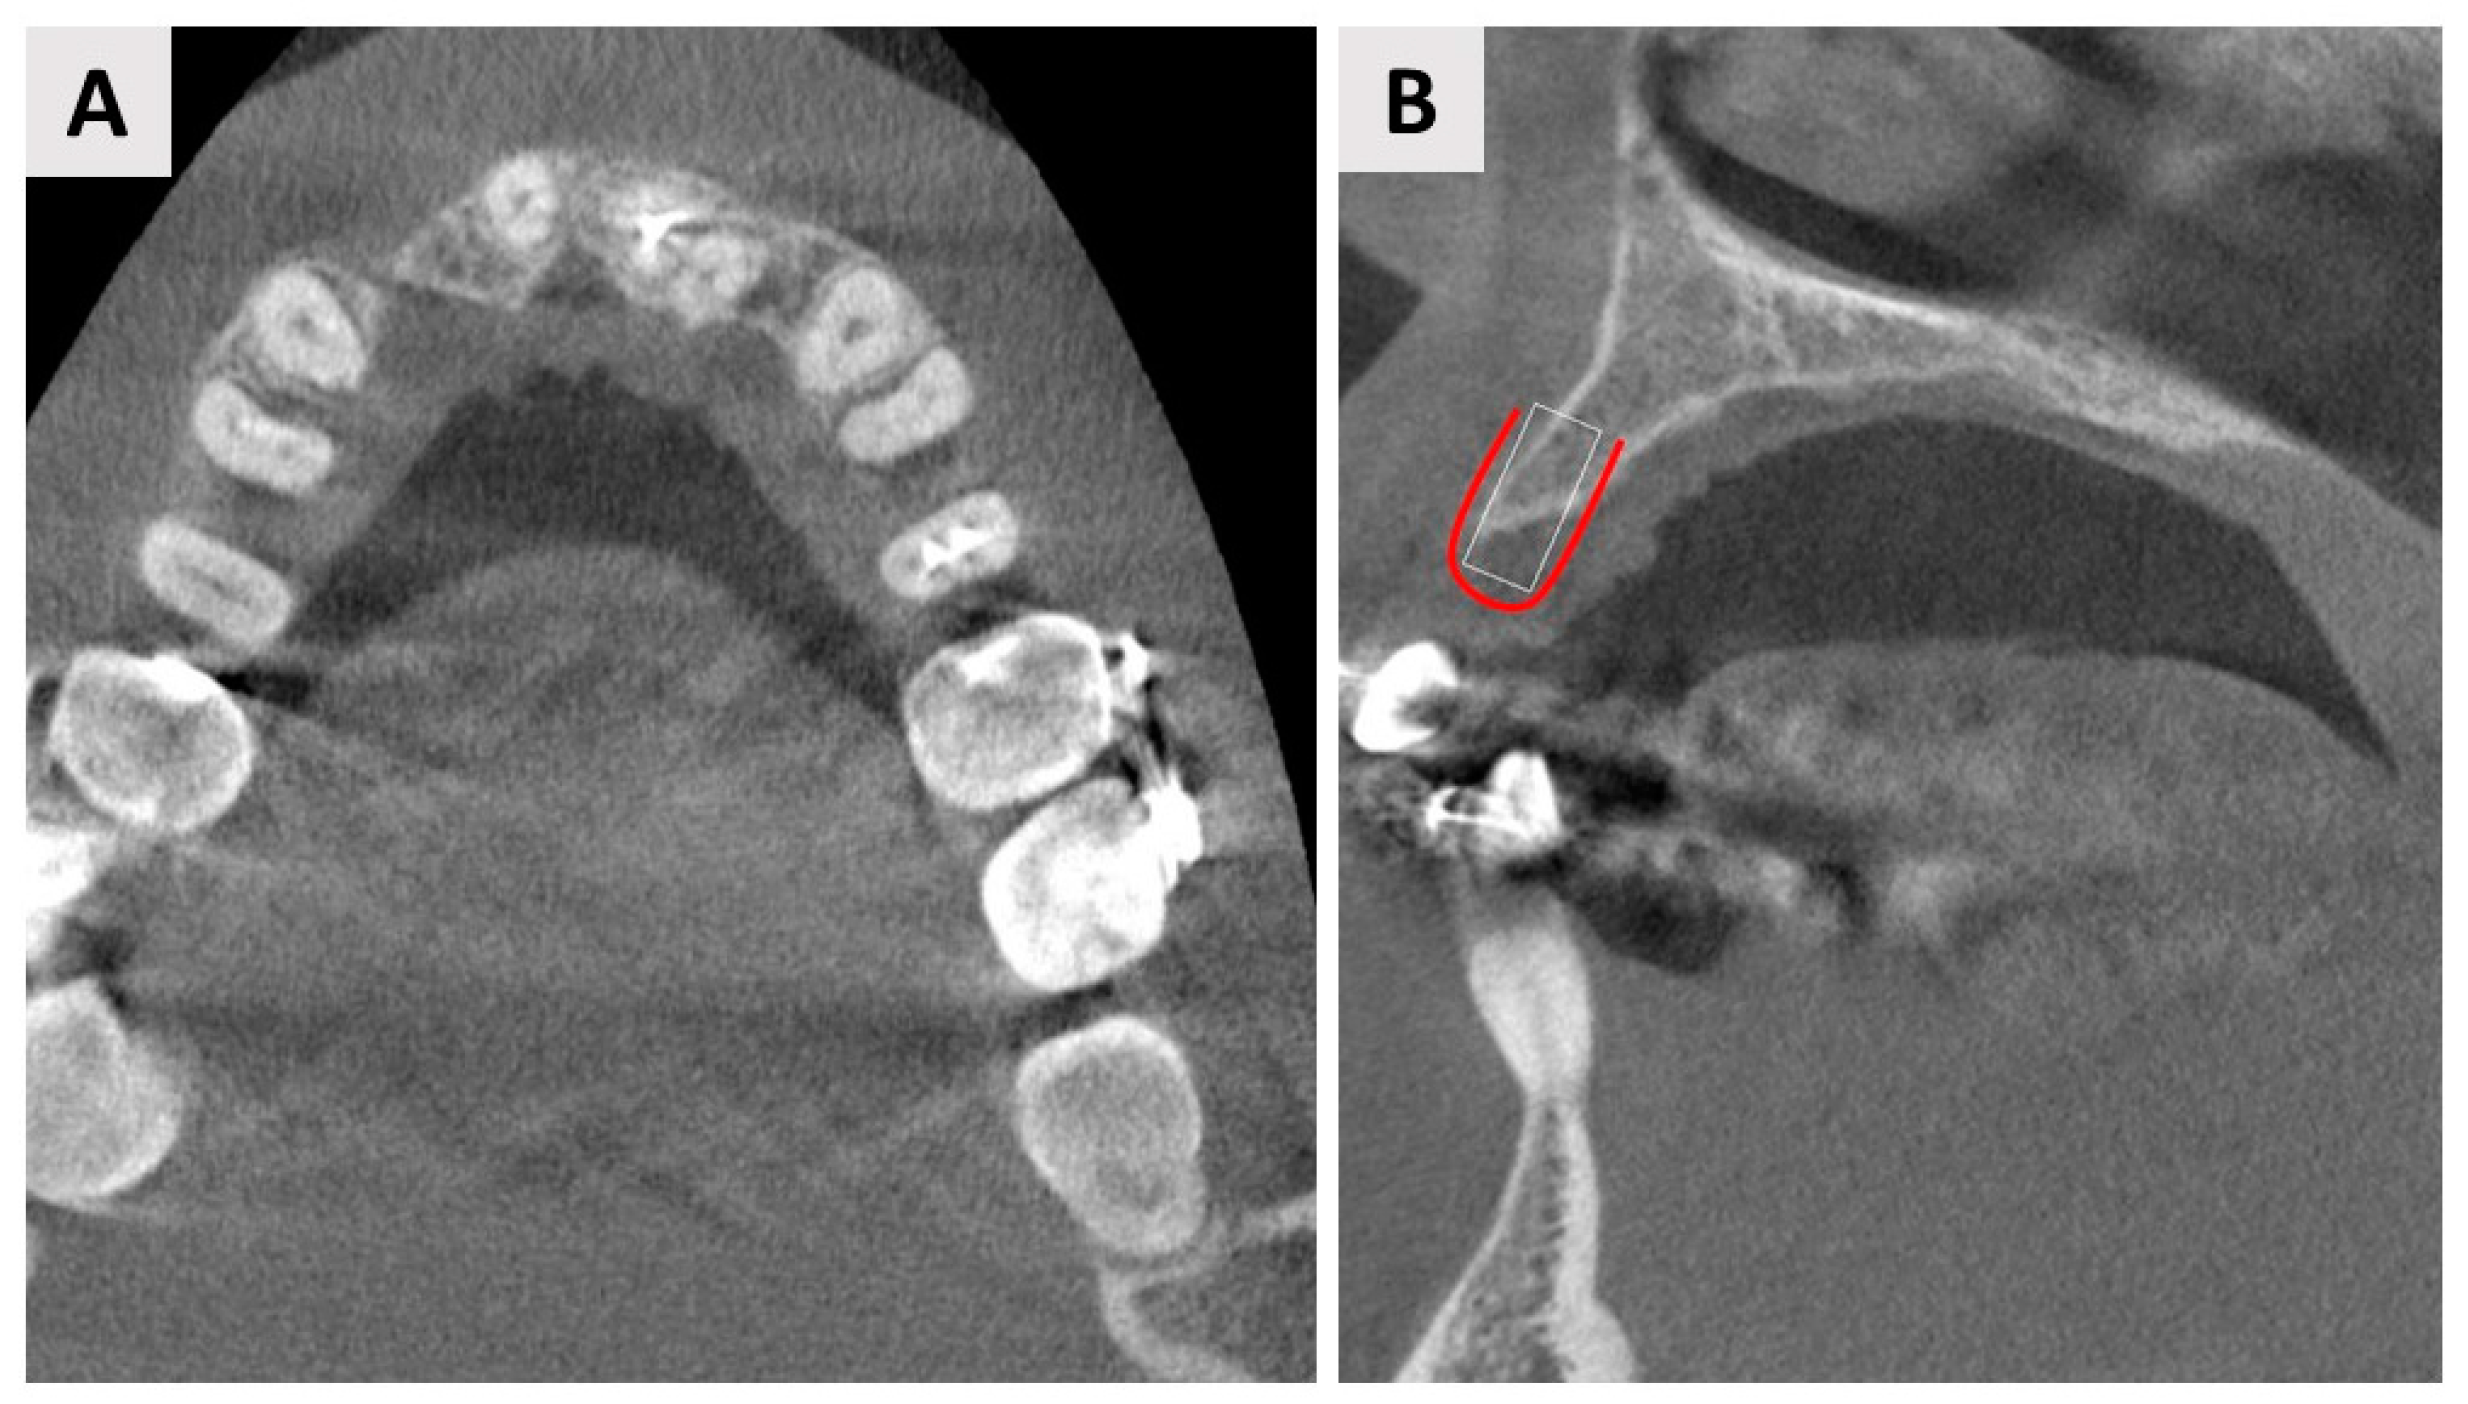

3. Case Report One: GBR with Delayed Implant Placement